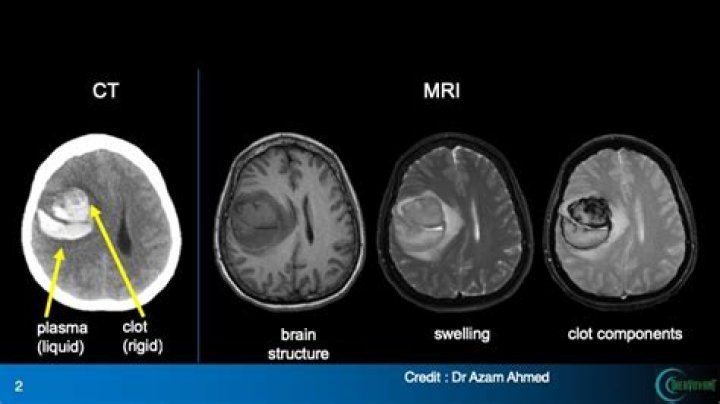

Brain magnetic resonance imaging (MRI) is the preferred and most sensitive modality after transient ischemic attack (TIA) or minor stroke. It should inclu...